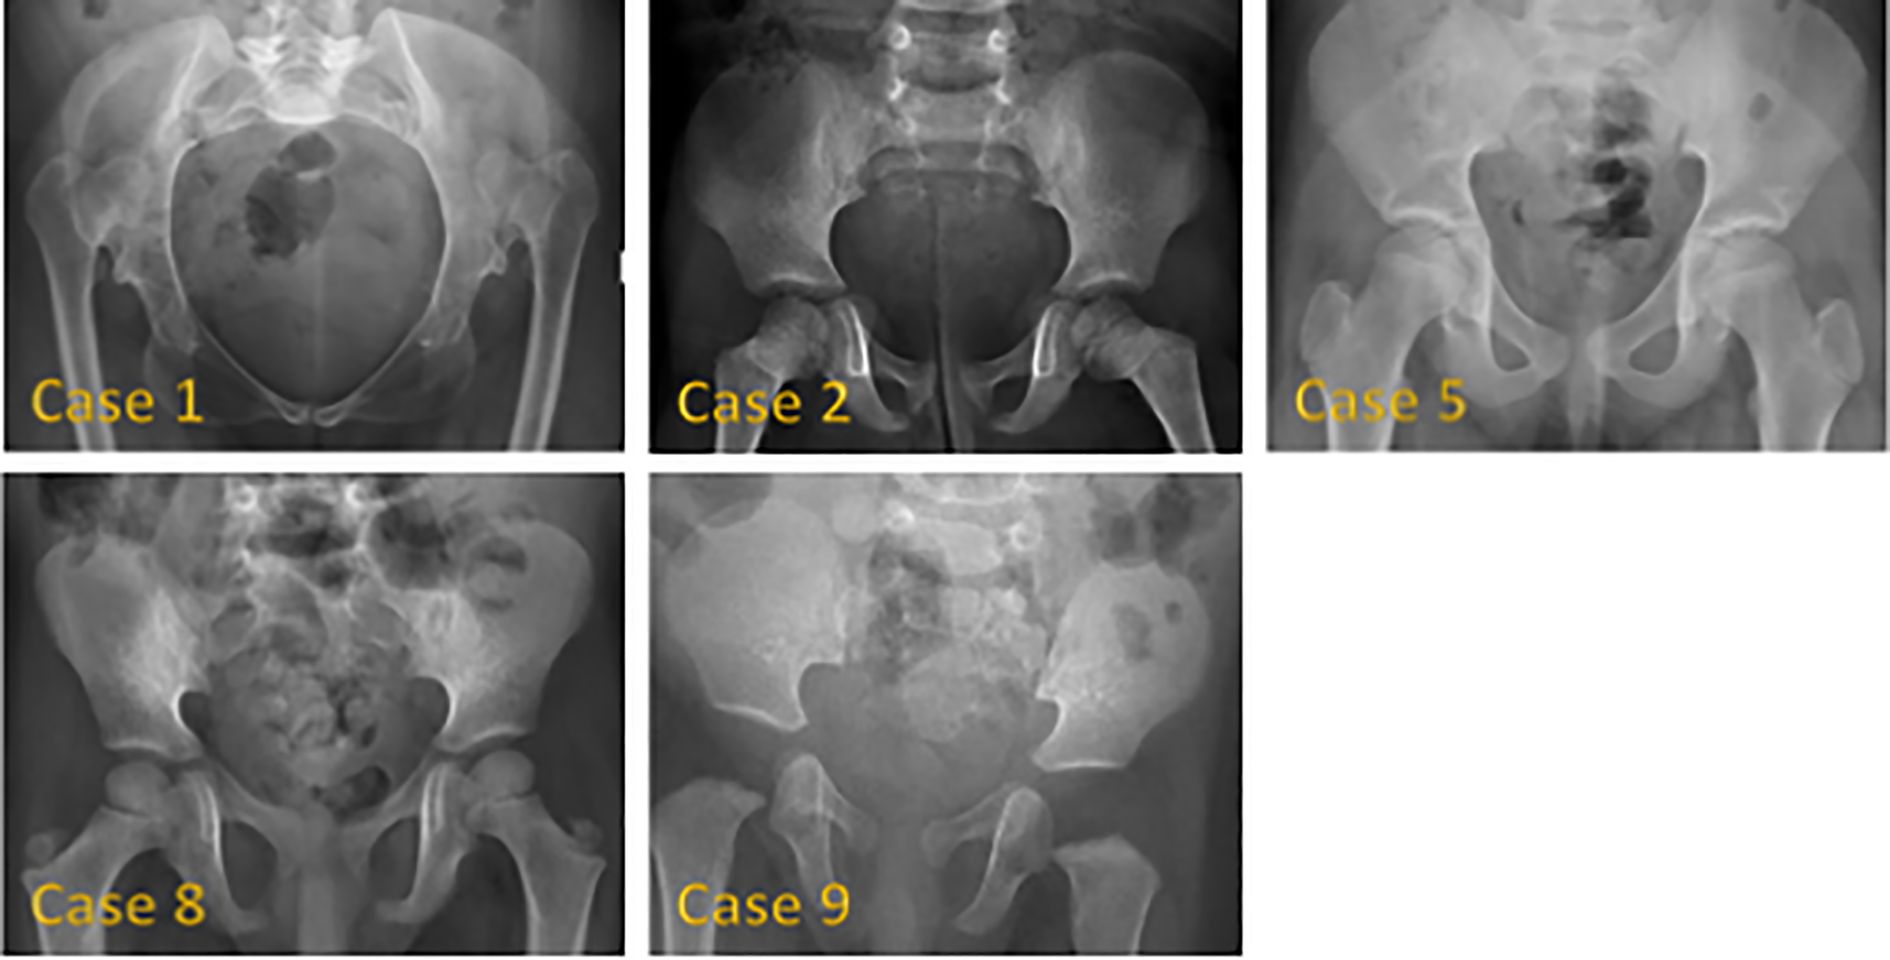

Background: 3M syndrome (3MS) is a very rare autosomal recessive disorder characterized by short stature, distinctive facial features, and skeletal abnormalities. The condition is frequently underdiagnosed due to its nonspecific symptoms and normal neurocognitive development. Few reports exist on its clinical course and response to growth hormone (GH) therapy. Therefore, this study aims to describe the clinical features of Saudi patients with 3MS and to investigate the effects of growth hormone therapy on growth. Methods: We conducted a retrospective case series of 14 Saudi patients from 11 families with genetically confirmed 3MS at King Faisal Specialist Hospital and Research Centre in Riyadh. Results: The mean age at diagnosis was 5.4 years. Consanguinity was present in 79% of cases. The most frequently affected gene was CUL7 (57% of cases), followed by OBSL1 and CCDC8. All variants were predominantly homozygous and classified as pathogenic or likely pathogenic. Clinical abnormalities included growth retardation, dental abnormalities, spinal abnormalities, and a This is a provisional file, not the final typeset article characteristic facial appearance. GH therapy was administered to 10 children; 5 demonstrated a measurable improvement in growth velocity, while 5 did not respond or discontinued treatment. IGF-1 was within/low-normal in most tested cases, with two elevated results. Conclusion: Our study highlights the extensive phenotypic variability of 3MS and underscores the predominantly autosomal recessive inheritance pattern in this population. GH therapy may provide a growth benefit in select cases, although resistance and poor response remain a challenge. Genetic testing is crucial for accurate diagnosis, individualized management, and appropriate family counseling.